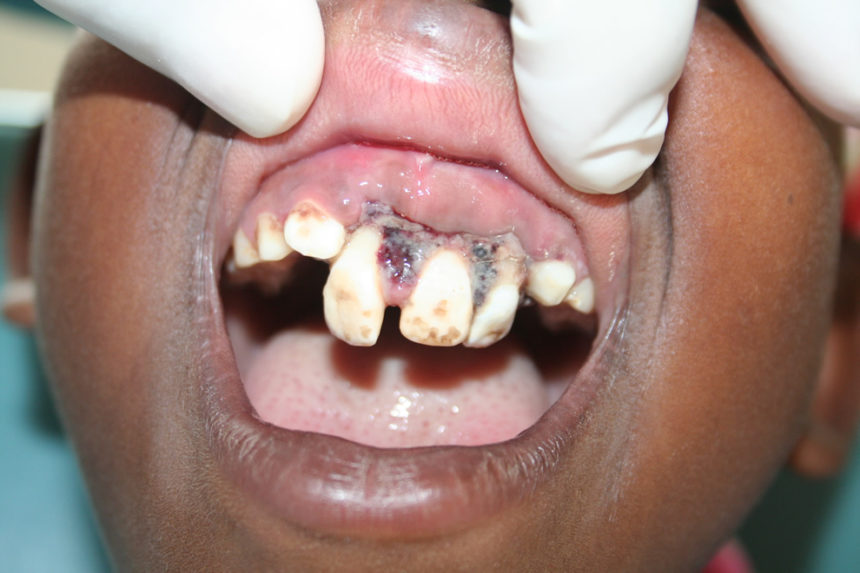

Kva er det så som møter ein tannlege som drar ut til ”the middle of nowhere”? Det er litt av kvart og det er svært sannsynleg at det vil dukke opp kasus som vi elles ser berre i lærebøker og patologiatlas.

Elles: To mandibelfrakturar, ein tumor som omfatta heile mellomansiktet på ei side og ei plommestor cyste i ganen.

Dei som kjem og søkjer hjelp har akutte problem. Det er smerter frå tenner med for store kariesangrep og det er små og store abscessar. Derfor er det ekstraksjon av molarar det dreier seg om! Retinerte visdomstenner er uvanleg.